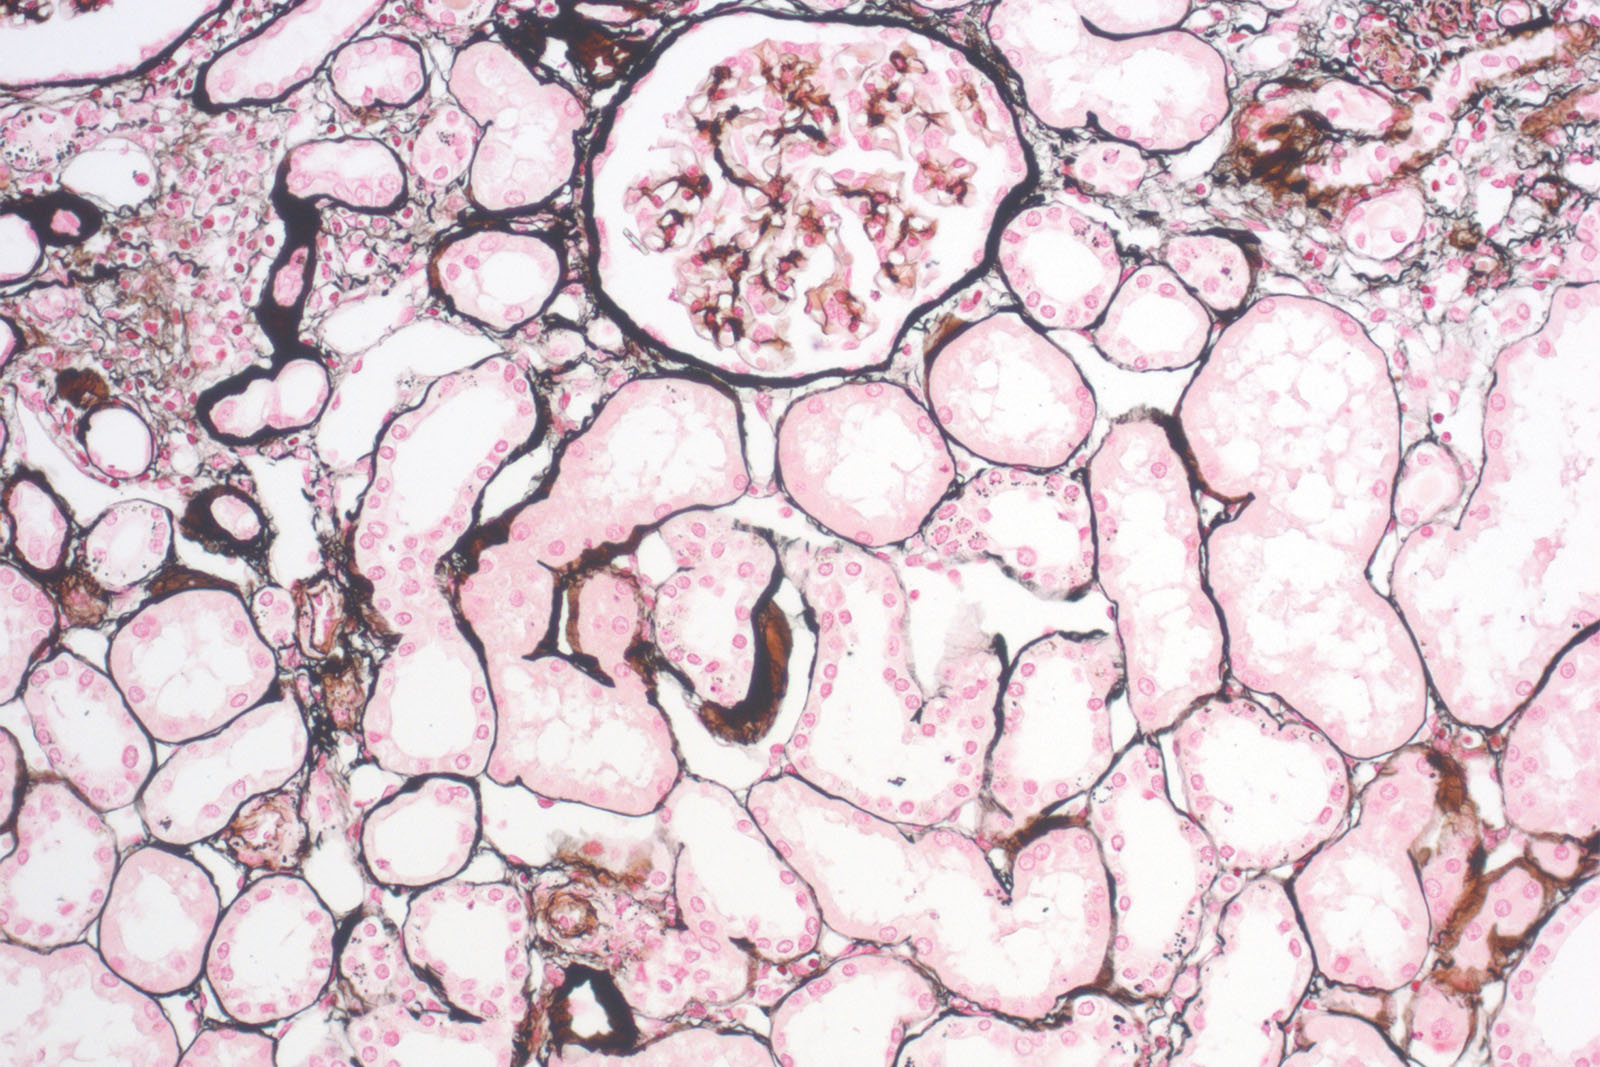

P.A.S.M. / Jones kit is used in histology for visualizing argentaffin structures, especially kidney membranes, but also fungi and certain pathogen organisms. Staining procedure starts with periodic acid solution being used to oxidize 1,2-glycols to aldehydes. During incubation in silver-methenamine-borate working solution aldehydes are reduced and at the same time cause reduction of silver ions to metallic silver that manifests as brown to black structures on the section. This is followed by toning the solution with gold chloride solution that additionally improves staining intensity of target structures (fungi, basal membranes and others), and it reduces background staining. Excessive unbound silver-gold bonds is removed by rinsing the section with sodium thiosulfate solution. Finally, the sections are exposed to Nuclear Fast Red (Kernechtrot) counterstain that stains background structures red; that in turn creates clear and visually rich contrast to target structures (colored in brown-black).